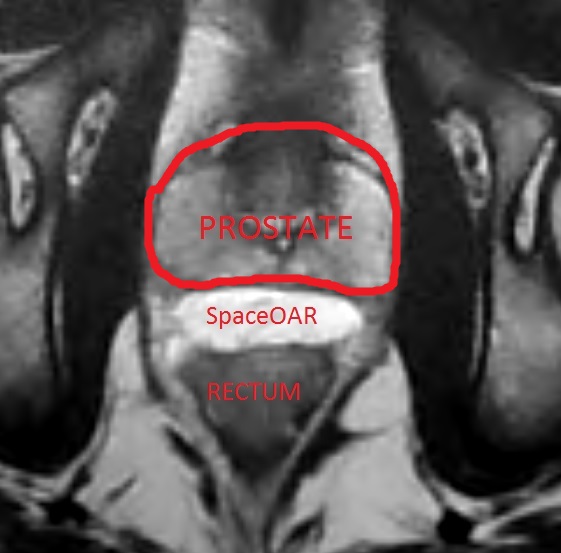

SpaceOAR hydrogel is an exciting addition to prostate radiation therapy. Currently only a handful of centers across the country are using this technology. A gel is injected into the tissue space in between the prostate gland and the rectum. Usually those two organs are directly against each other, but by injecting a gel we can push them apart. This results in less radiation dose reaching the rectum! With less radiation dose there are clinically proven fewer rectal side effects, and a smaller chance of rectal complications. With SpaceOAR there may also be less radiation reaching the penile bulb, and less erectile dysfunction.

Approximately 10cc (1/3 ounce) of two liquids are simultaneously injected via a Y connector and a long needle into the tissue space between the prostate and the rectum. When those two liquids mix together they create a firm gel in the tissue space. The gel remains there for about 3 months and then begins to break down, eventually being completely absorbed by the body.

SpaceOAR does not usually cause side effects, but occasionally men have report a peculiar sensation or discomfort in the rectal area, which usually subsides in a few days. SpaceOAR can be used with any type of prostate radiation treatment, whether that be IMRT, proton therapy, brachytherapy, or CyberKnife/SBRT. In the picture below, the white area in between the prostate and the rectum is the hydrogel which I have injected, pushing the two nicely apart. They would normally be directly against each other.